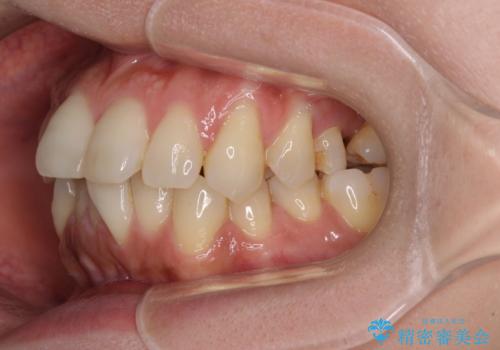

- 全体的なデコボコと、以前抜歯した歯のスペースを閉じた部分が気になるとのことで来院された患者様です。

左上第一大臼歯を抜歯した際に、スペースを閉じたそうですが、歯が傾斜してものが挟まって不快とのことでした。

インビザライン矯正で全体の歯列と整えるとともに、左上第一大臼歯部にはスペースを作り、インプラントによる補綴治療を行うこととしました。